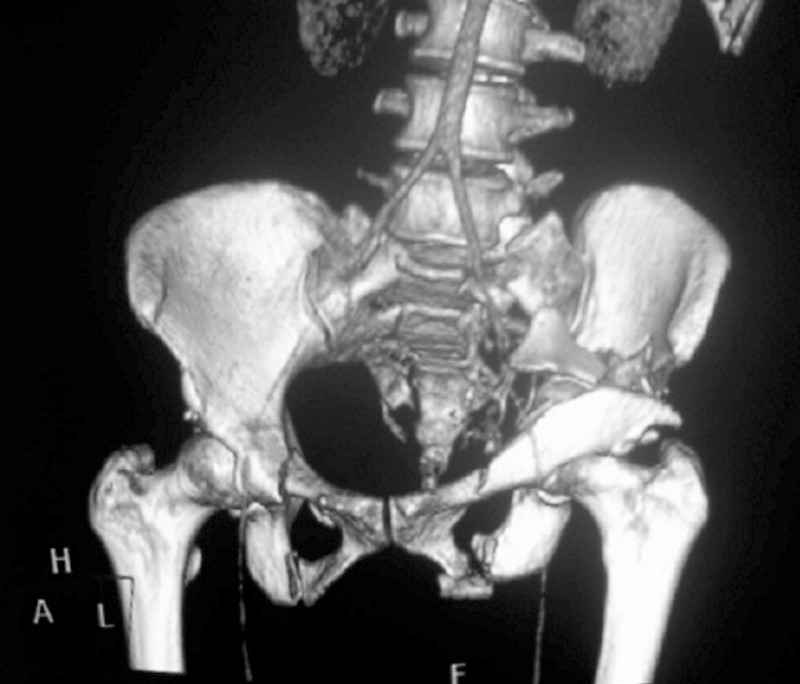

This patient has extensive and complicated skeletal injuries...much more data (such as additional relevant images and clinical information regarding the soft tissues and overall patient status) would help us formulate an informed plan.

The sacral pattern alone is quite difficult and seems to be some version of an H-pattern, but I can’t tell from these films.

General condition is fine except for an intractable pelvic pain, no associated injuries (only ankle fracture), no sciatic nerve injury.

The soft tissues are also in mild condition, buttock hematoma and probably a Morel-Lavalle. I send some more CT images. There are some conminution in the posterior column (I don’t have images now). The patient is scheduled for surgery next Monday. The plan is percutaneous sacral fixation and then ilioinguinal approach .

I am a huge fan of closed reduction and percutaneous posterior pelvic fixation, but that particular sacral injury warrants an open reduction.

I’d begin with that in order to have a high quality osseus foundation for subsequent acetabular repair.